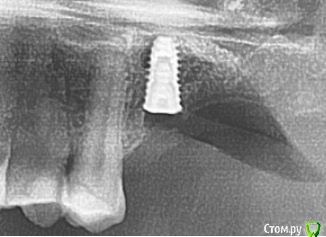

kamranchick Опубликовано 23 февраля, 2018 Поделиться Опубликовано 23 февраля, 2018 Спасибо,через 6 мес буду ставить 1 имплант в область 2.6.Да, вижу, что получился зиккурат, я еще плохо себе представляю как рассчитать соотношение высоты к основанию объёма,для наметки высоты я засверливаюсь на 3мм ниже будущей "вершины" или "будущего дна пазухи", не понимаю где будут границы основания.и старайтесь доводить до медиальной стенки. 1 Ссылка на комментарий

Sampson Опубликовано 24 февраля, 2018 Поделиться Опубликовано 24 февраля, 2018 (изменено) А сразу имплант что не поставили?При планировании было желание рискнуть, попробовать,но опыта пока мало, суммарно я поставил 20 имплантов. Первый синус с установкой, так вообще бывает? Изменено 24 февраля, 2018 пользователем Sampson Ссылка на комментарий